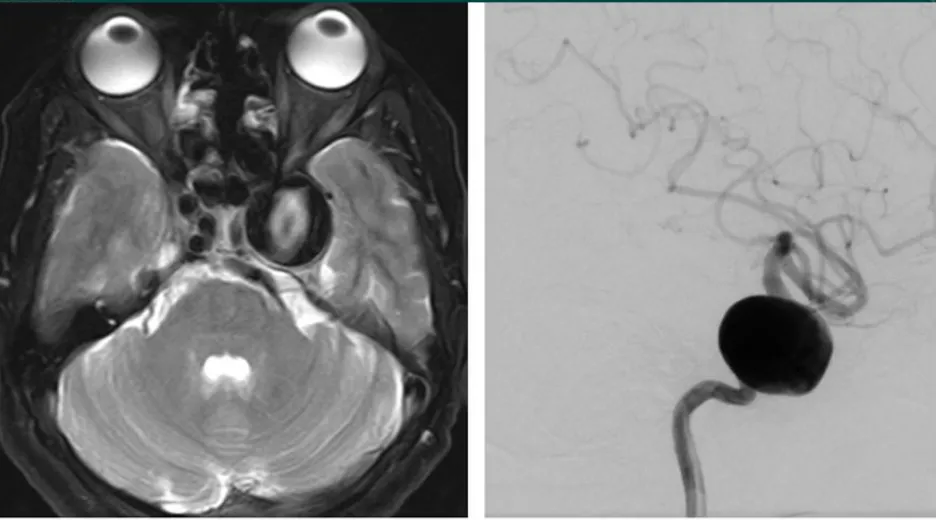

海绵窦脑膜瘤合并左侧颈内动脉狭窄,手术难度显著增加

海绵状神经鞘瘤,瘤内可见囊性变,实性部分强化明显

海绵窦血管瘤,T2加权像呈高信号,累及左侧Meckel腔

海绵窦区颈内动脉瘤